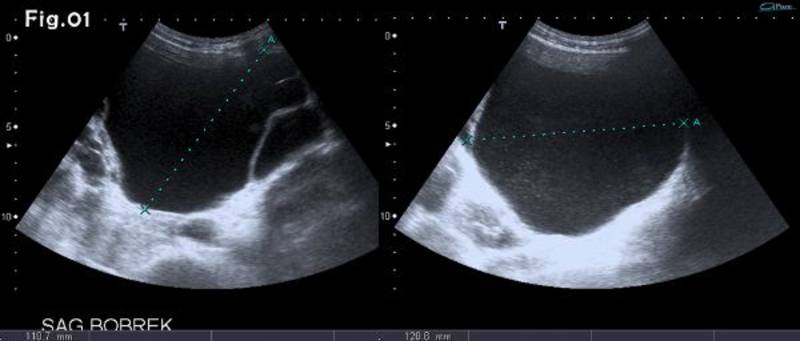

55 gadus vecs vīrietis ar autosomāli dominantu policistisku nieru slimību iestājās ar masīvu hematūriju un tika nosūtīts uz ultrasonogrāfijas (USG) izmeklējumu. USG tika rūpīgi izmeklētas abas lielās nieres, lai atrastu hematūrijas cēloni. Lielāko cistu maksimālais diametrs bija 120 mm kreisajā pusē un 102 mm labajā pusē. Kreisās puses cistai bija multipli sīki iekšēji ehogēni fokusi (1. attēls).